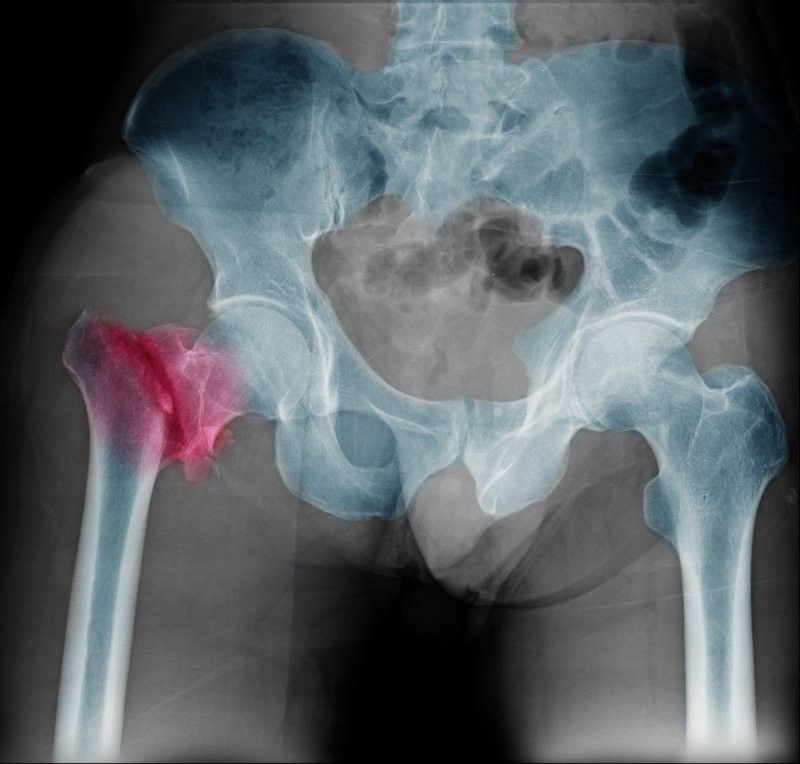

Согласно официальным данным, каждая третья женщина и каждый пятый мужчина старше 50 лет в России страдает остеопорозом.Заболевание развивается медленно, в течение нескольких лет. Часто его диагностируют, когда перелом происходит из-за падения или удара.Самые частые переломы - запястья, шейки бедра и позвонков.Слабость костей может быть такой сильной, что даже кашель или чихание вызовут перелом ребра или повреждение позвоночника.Сутулость, при которой человек выглядит наклонённым вперёд, часто становится первым признаком болезни у пожилых. Эта поза появляется из-за ломкости костей в позвоночнике, что мешает поддерживать тело в вертикальном положении.